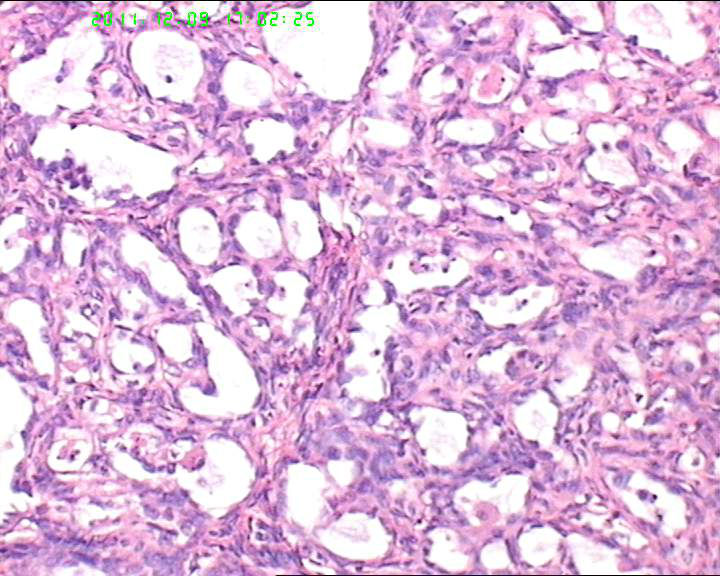

盆腔包块4个月,13*8*7cm 大小,囊实性,实性区菜花状、灰白质脆,局部半透明。

筛状迷路样结构,部分呈乳头状,异型明显,S-D小体不明显,考虑卵黄囊瘤。做CK,AFP,AAT.

首先考虑透明细胞癌,鉴别卵黄囊瘤

有腺腔样结构,内衬靴钉样细胞,还可见透明细胞,首先考虑透明细胞癌,鉴别诊断:内胚窦瘤。内胚窦瘤的网状结构内衬是扁平的上皮。

肿瘤细胞弥漫性生长,细胞排列成腺样、腺泡状,细胞异型明显。突向腔内。

卵巢生殖细胞肿瘤,卵黄囊瘤;

性索间质肿瘤,颗粒细胞瘤;

转移性的癌

有鞋钉样细胞,首先考虑透明细胞癌。要除外卵黄囊瘤,浆乳癌。